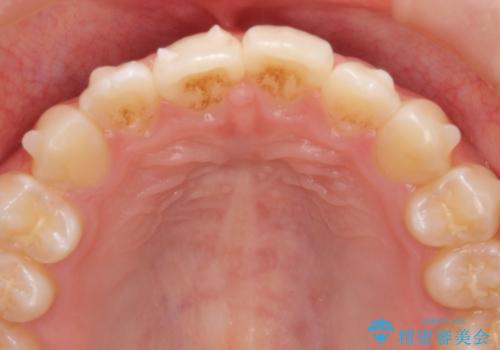

インビザラインライトで行う短期マウスピース矯正治療

- 前歯のガタつきを並べたいたいと、矯正治療を希望され来院されました。

とにかく短期間で前歯だけの治療を行いという希望が強く、全体矯正と前歯だけの部分矯正の仕上がりのイメージを確認したのち14枚のマウスピースで前歯のみの矯正治療を行っていくこととしました。

インビザラインライトは軽度なガタつきや傾斜の改善に用いられる全14枚のマウスピース矯正です。